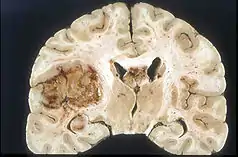

Macroscopic pathology of glioblastoma.

The Kernohan grading system[4][5] defines progressive malignancy of astrocytomas as follows:

• Grade 1 tumors are benign astrocytomas.

• Grade 2 tumors are low-grade astrocytomas.

• Grade 3 tumors are anaplastic astrocytomas.

• Grade 4 tumors are glioblastomas.